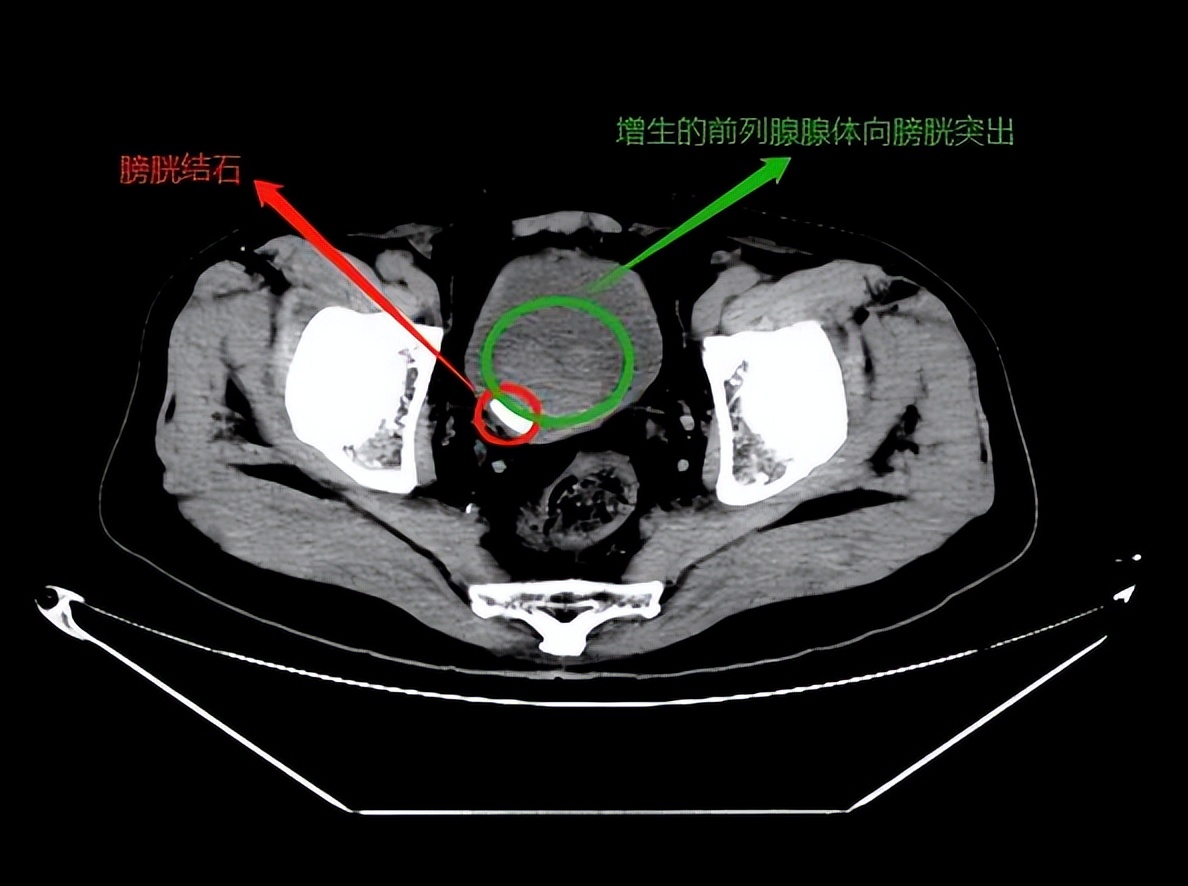

通过彩色超声波检查显示:前列腺增生,伴有膀胱多发性结石。

前列腺增生后,表面黏膜上毛细血管充血及扩张,容易破裂出血。 上面描述的尿潴留症状,如果得不到及时处理,会导致双肾积水,影响肾功能,严重时出现尿毒症。长期排尿不畅、膀胱内残留尿液会引发泌尿系感染,混浊的尿液沉积还会形成膀胱结石。